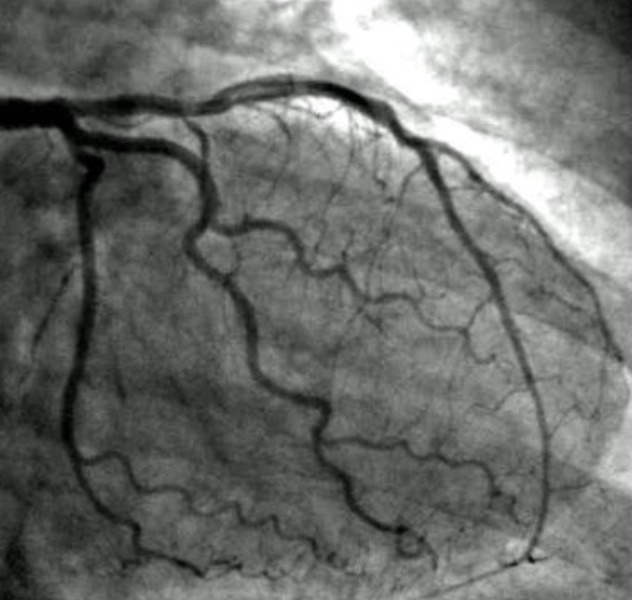

Angiogram test in Bangalore is often recommended when doctors need a precise understanding of the condition of the coronary arteries. Many patients visit Dr. Kumar Kenchappa in Bangalore when they experience persistent chest discomfort, breathlessness during routine activity, or unusual fatigue. These symptoms sometimes indicate restricted blood flow to the heart. An angiogram test helps doctors clearly visualize the arteries and determine whether there are blockages or narrowing that require treatment.

The angiogram procedure involves inserting a thin catheter through a blood vessel and guiding it toward the heart. A special contrast dye is then injected, allowing the arteries to appear clearly on imaging equipment. This enables the cardiologist to examine the flow of blood through the coronary arteries in detail. The results help determine whether lifestyle changes, medication, or procedures such as angioplasty are necessary. Patients often feel reassured after the test because it provides clarity about their heart condition.